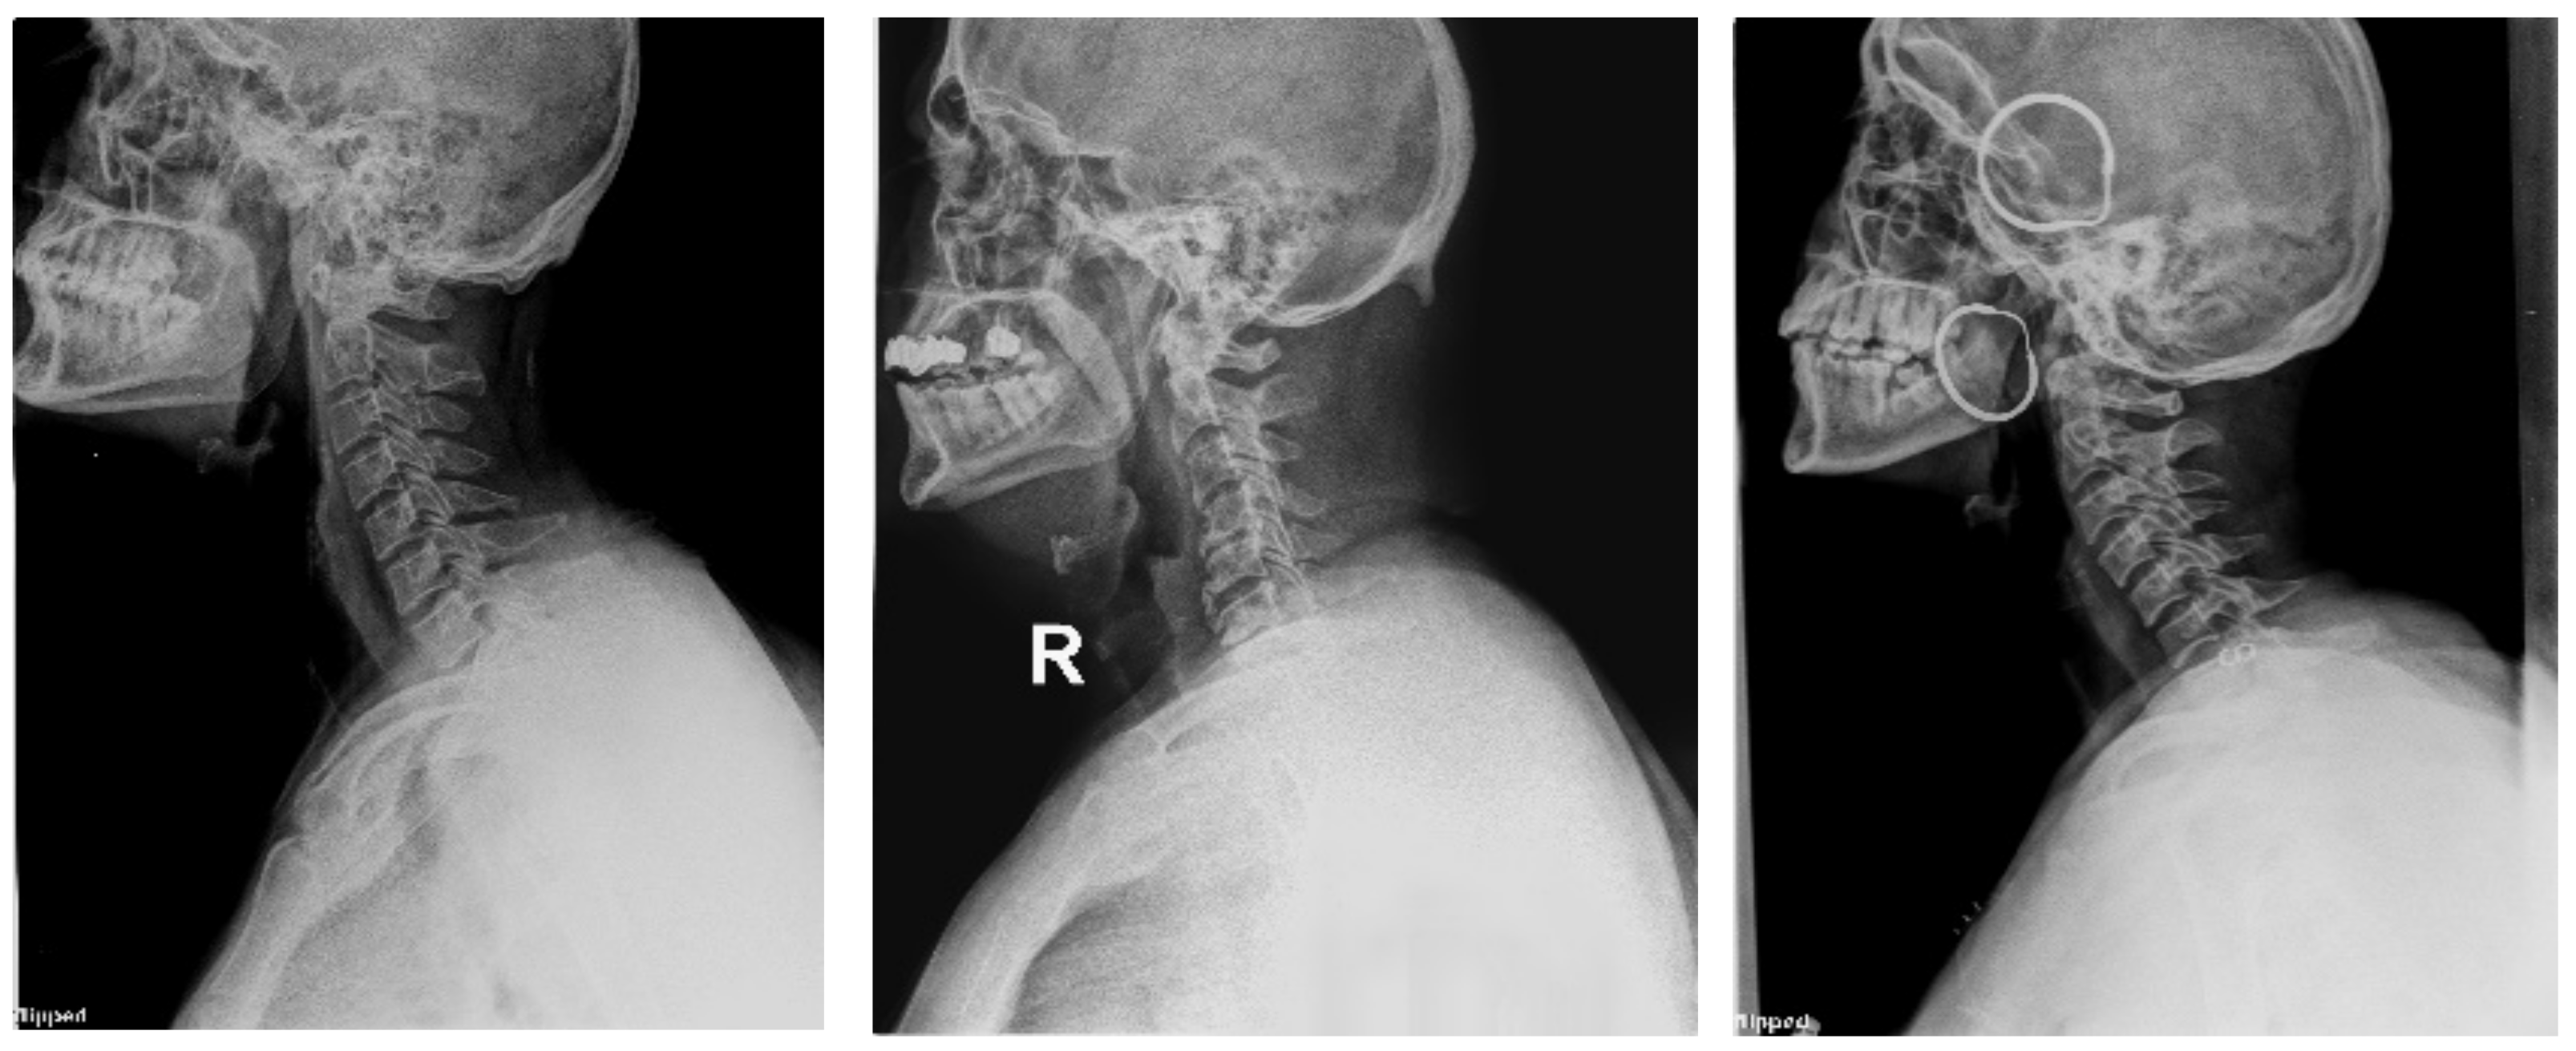

4.1.2. Clinical Case Study

4.1.3. Saliency Map